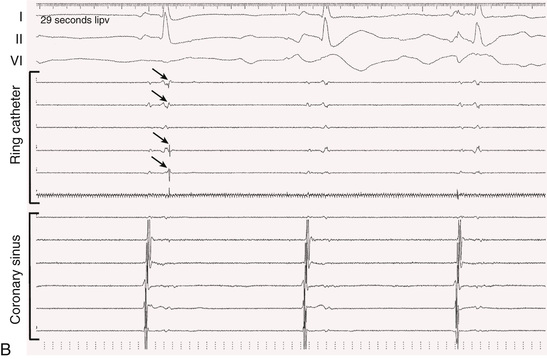

A multielectrode catheter inserted through a central lumen of the cryoballoon catheter often allows recording of PV potentials during an application of cryoenergy. Disappearance or dissociation of PV potentials within the first minute of a cryoenergy application is a strong independent predictor of durable PV isolation64 (Fig. 38.10). Other independent predictors are achieving a balloon temperature of −40°C in less than 60 seconds during an application of cryoenergy and an interval thaw time to 0°C of longer than 10 seconds on completion of a cryoenergy application.64,65